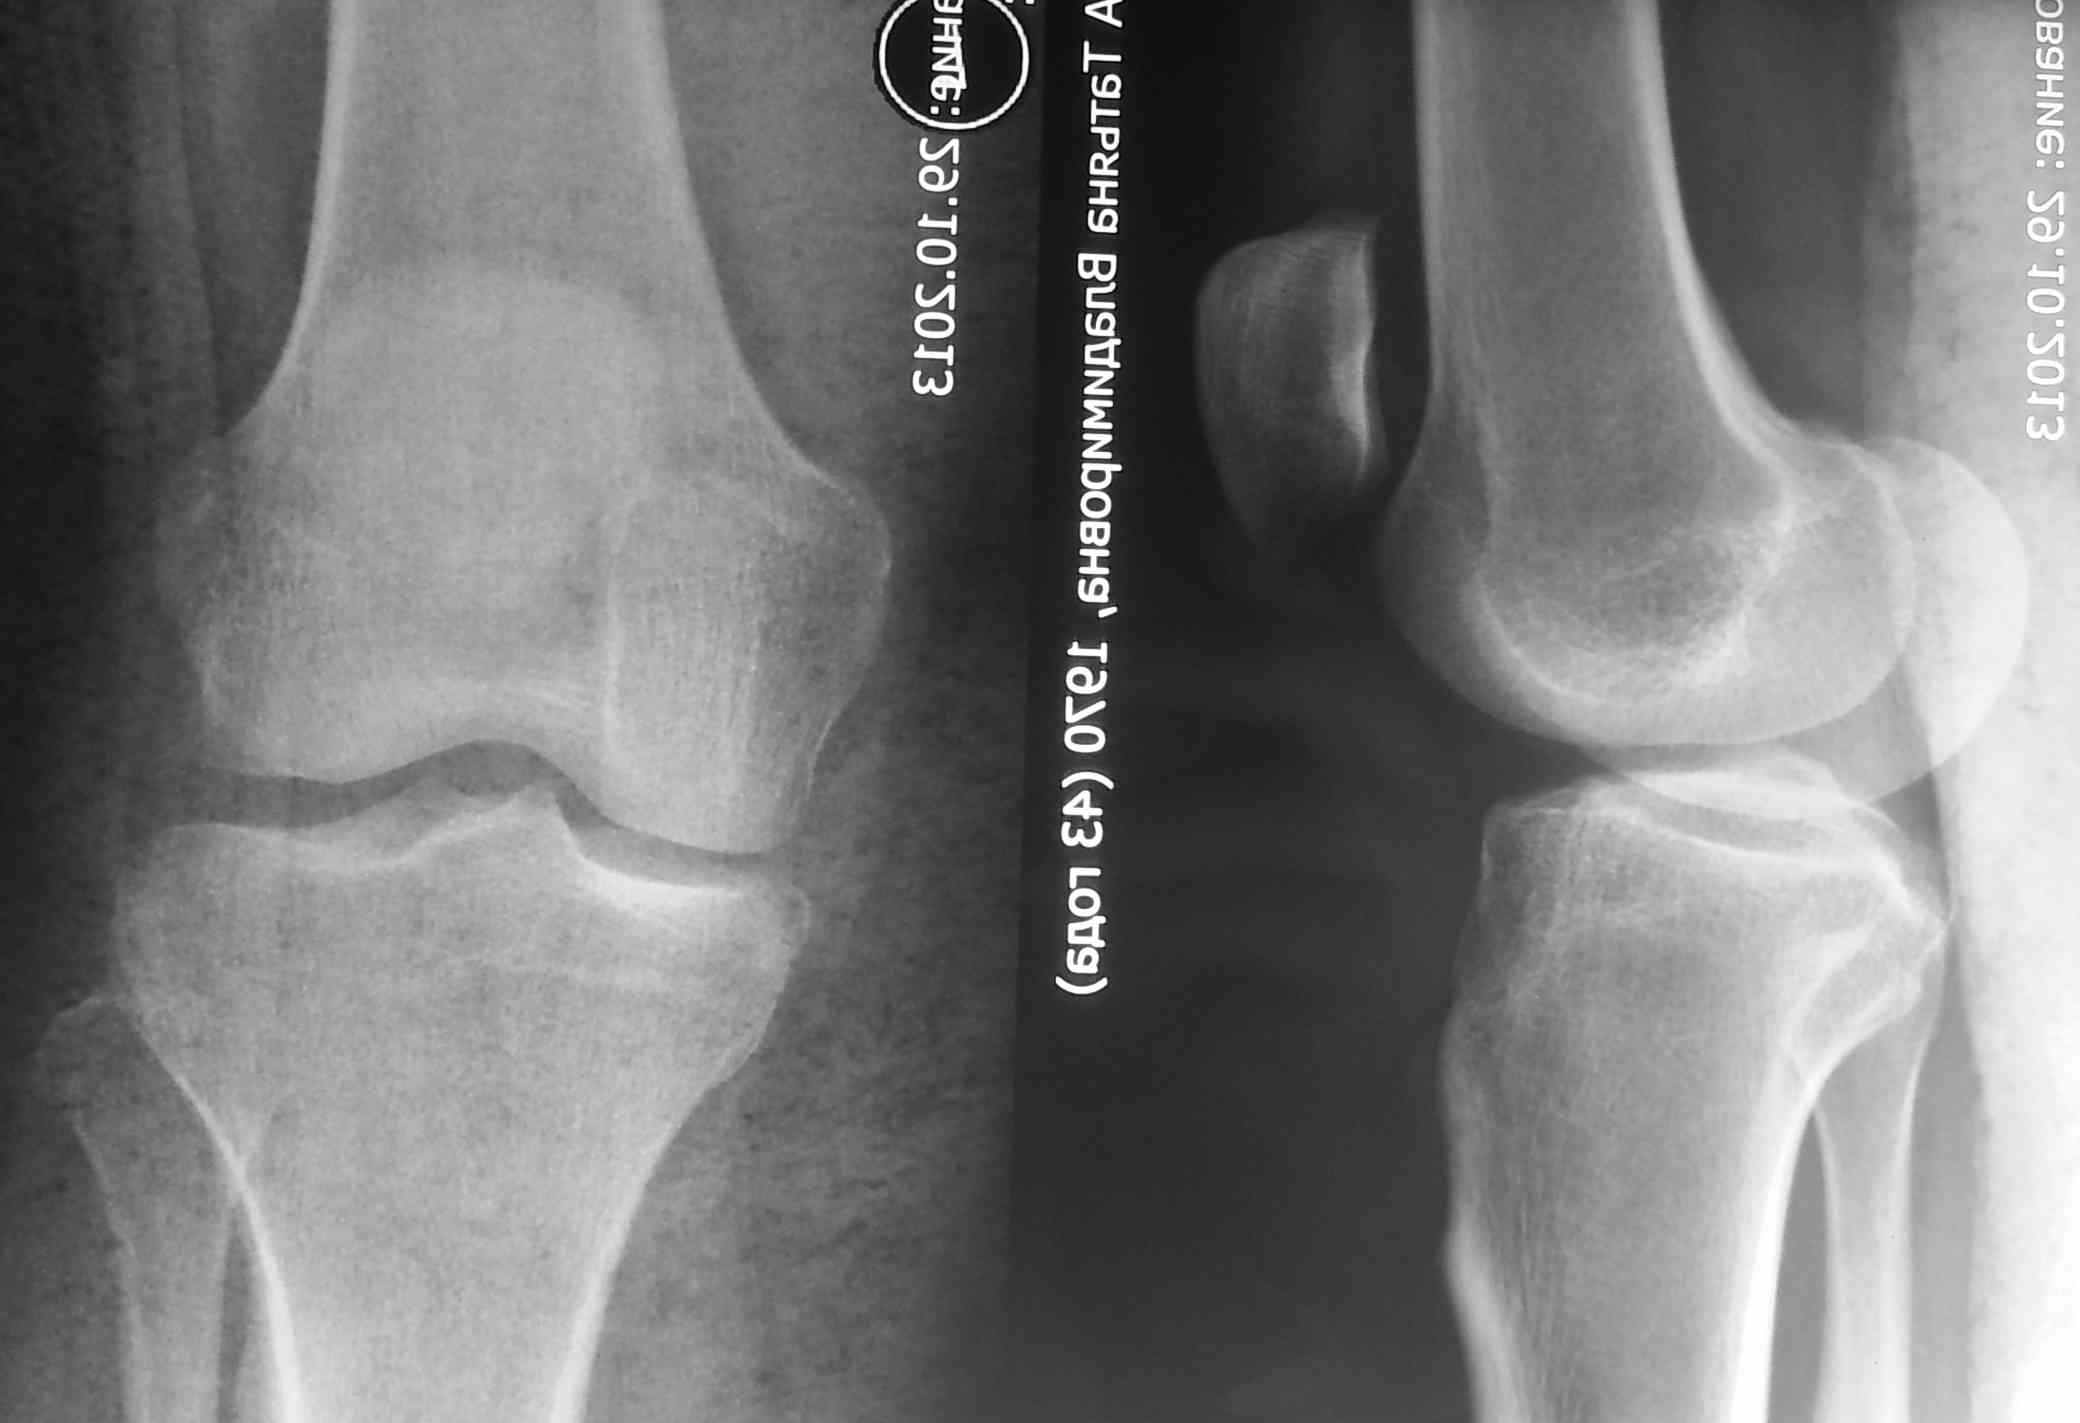

привычный вывих надколенника + patella alta

Обратилась молодая женщина с повторным вывихом надколенника, повторный вывих в октябре 2013. после чего находилась в гипсе и ортезе. Сейчас сгибание - 90. Снимки прилагаю. Планирую латеральный релиз и medial plication. Достаточно ли этого будет? Другие варианты?